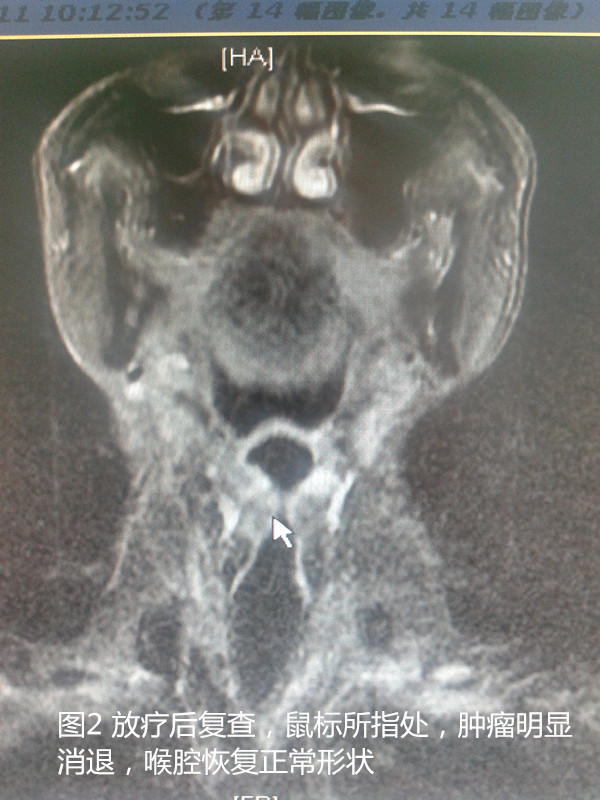

后来患者找到了沭阳县人民医院肿瘤科专家姚型锋。姚主任介绍:喉癌是头颈部常见的恶性肿瘤之一,近年来喉癌的发病率有增多的趋势。喉癌常见临床症状有:声音嘶哑、咽喉部异物感、痰中带血、饮水呛咳等。自沭阳县人民医院开展三维适形、调强放疗以来,已治疗头颈部恶性肿瘤一百余例。处方剂量可达66-70Gy/33-35F。治疗效果确切,肿瘤明显消退,痛苦小,声音嘶哑、咽喉部不适能得到明显好转。同时姚主任提醒大家:凡是有不明原因的声音嘶哑、咽喉部异物感、咽下疼痛及痰中带血的病人,尤其是年龄超过40岁、嗜烟酒者均应做必要的检查。下图为上文介绍病例影像学资料前后比较,治疗前后MRI显示,喉腔肿瘤明显缩小,调强放疗治疗效果好。